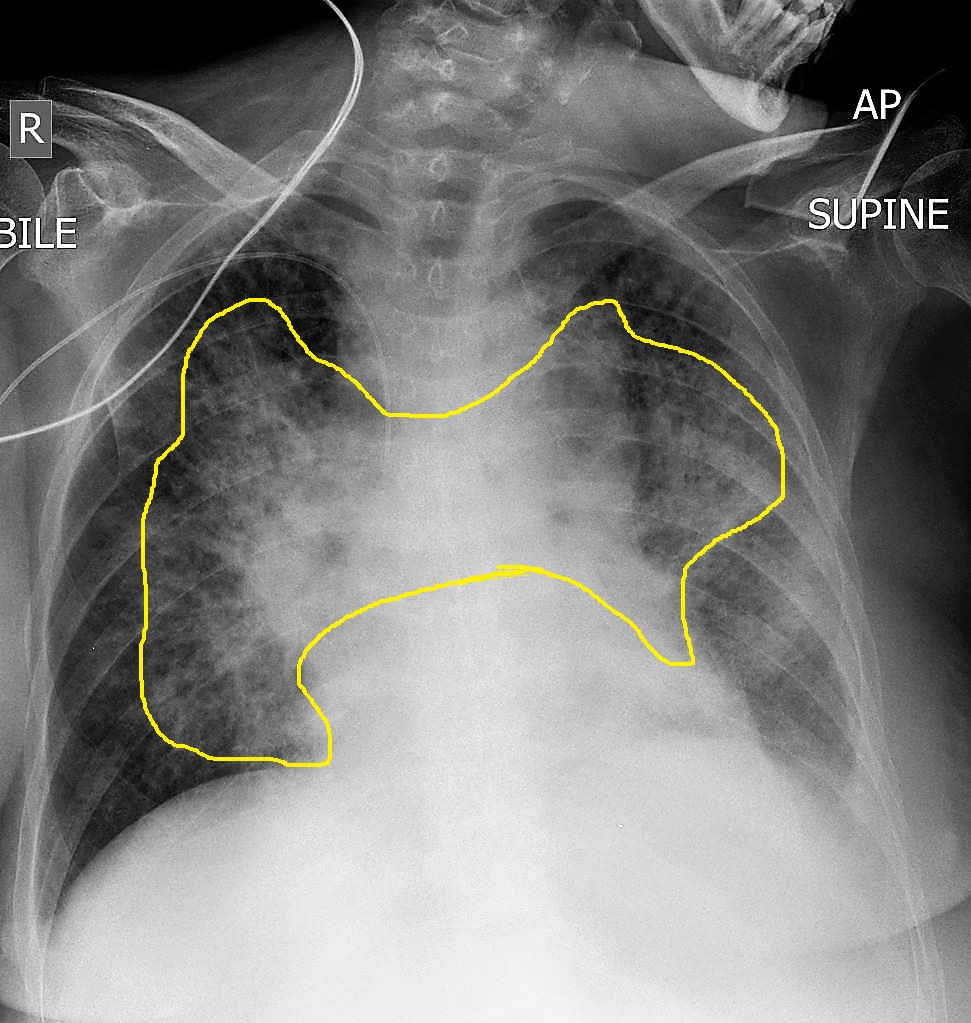

La tele de tórax es un tipo de radiografía en la que se utilizan rayos X para obtener imágenes detalladas de los órganos y tejidos dentro del tórax. Este examen se realiza con el paciente en posición erguida, generalmente de pie o sentado, para permitir una visión clara de los pulmones, el corazón, los vasos sanguíneos y las costillas. A veces, se puede realizar en posición acostada, dependiendo de la condición del paciente.

Se pueden realizar imágenes en diferentes vistas, como la posterior-anterior (PA), en la que el paciente se coloca con el pecho hacia el aparato de rayos X, y la lateral, en la que el paciente se coloca de lado. Durante el procedimiento, el paciente debe mantener una posición fija y seguir las indicaciones del técnico para evitar que las imágenes salgan borrosas. En ocasiones, se les pedirá que contengan la respiración por un breve momento para evitar que los movimientos respiratorios distorsionen la imagen.

Los pulmones son la principal área que se evalúa en una radiografía de tórax. Cualquier anomalía, como una infección, colapso pulmonar (neumotórax), o la presencia de masas, será visible en la imagen.

La presencia de infiltrados en una tele de torax sugiere un proceso patológico que afecta el intersticio o los espacios alveolares del pulmón. Estos hallazgos radiológicos se manifiestan como áreas de mayor opacidad en la placa, indicando acumulación de líquido, células o material exudativo. La identificación y caracterización de estos infiltrados permiten orientar el diagnóstico y definir el manejo clínico adecuado.

La presencia de infiltrados en una tele de torax sugiere un proceso patológico que afecta el intersticio o los espacios alveolares del pulmón. Estos hallazgos radiológicos se manifiestan como áreas de mayor opacidad en la placa, indicando acumulación de líquido, células o material exudativo. La identificación y caracterización de estos infiltrados permiten orientar el diagnóstico y definir el manejo clínico adecuado. Uno de los principales motivos por los que se solicita una tele de tórax antes de una cirugía es la evaluación del estado pulmonar del paciente. Algunas condiciones respiratorias pueden afectar la capacidad de oxigenación y la recuperación postoperatoria, entre ellas: